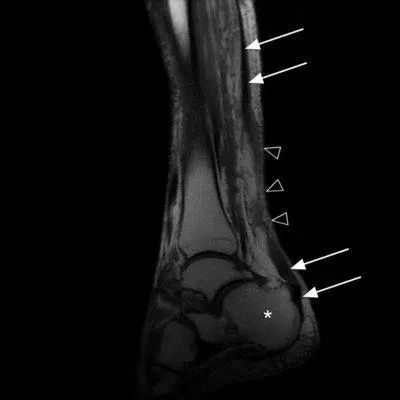

正后方看,可以看到粗黑长的跟腱再中间变得不连续了

白色箭头是跟腱 三角是断裂处

白色箭头是跟腱的断裂部位